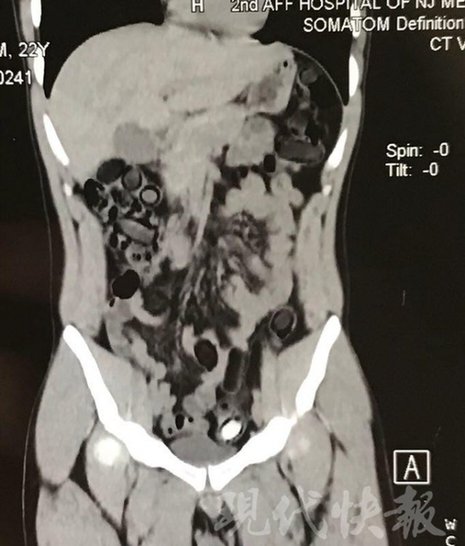

由于毒品在體內(nèi)一旦泄露有可能致命,警方第一時(shí)間將阿永帶到醫(yī)院進(jìn)行檢查。CT 掃描的結(jié)果顯示,阿永體內(nèi)布滿了密密麻麻的白色圓柱狀固體,就像一粒粒的蠶蛹。在南京市公安局鼓樓分局二板橋派出所,阿永分四次排出了毒品,毛重369.99克。經(jīng)訊問,阿永交代了自己全部的犯罪事實(shí)。目前,阿永已被刑事拘留。